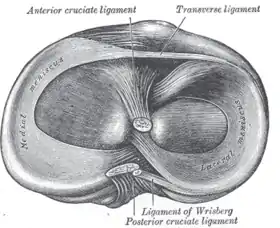

Head of right tibia seen from above, showing menisci and attachments of ligaments.